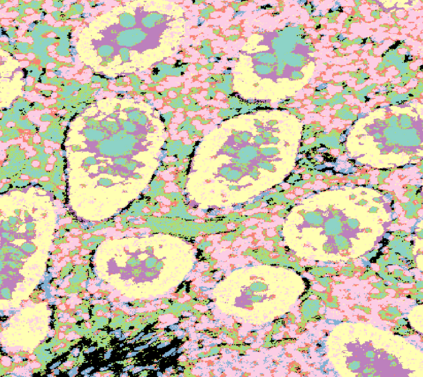

The usage of chemical imaging technologies is becoming a routine accompaniment to traditional methods in pathology. Significant technological advances have developed these next generation techniques to provide rich, spatially resolved, multidimensional chemical images. The rise of digital pathology has significantly enhanced the synergy of these imaging modalities with optical microscopy and immunohistochemistry, enhancing our understanding of the biological mechanisms and progression of diseases. Techniques such as imaging mass cytometry provide labelled multidimensional (multiplex) images of specific components used in conjunction with digital pathology techniques. These powerful techniques generate a wealth of high dimensional data that create significant challenges in data analysis. Unsupervised methods such as clustering are an attractive way to analyse these data, however, they require the selection of parameters such as the number of clusters. Here we propose a methodology to estimate the number of clusters in an automatic data-driven manner using a deep sparse autoencoder to embed the data into a lower dimensional space. We compute the density of regions in the embedded space, the majority of which are empty, enabling the high density regions to be detected as outliers and provide an estimate for the number of clusters. This framework provides a fully unsupervised and data-driven method to analyse multidimensional data. In this work we demonstrate our method using 45 multiplex imaging mass cytometry datasets. Moreover, our model is trained using only one of the datasets and the learned embedding is applied to the remaining 44 images providing an efficient process for data analysis. Finally, we demonstrate the high computational efficiency of our method which is two orders of magnitude faster than estimating via computing the sum squared distances as a function of cluster number.